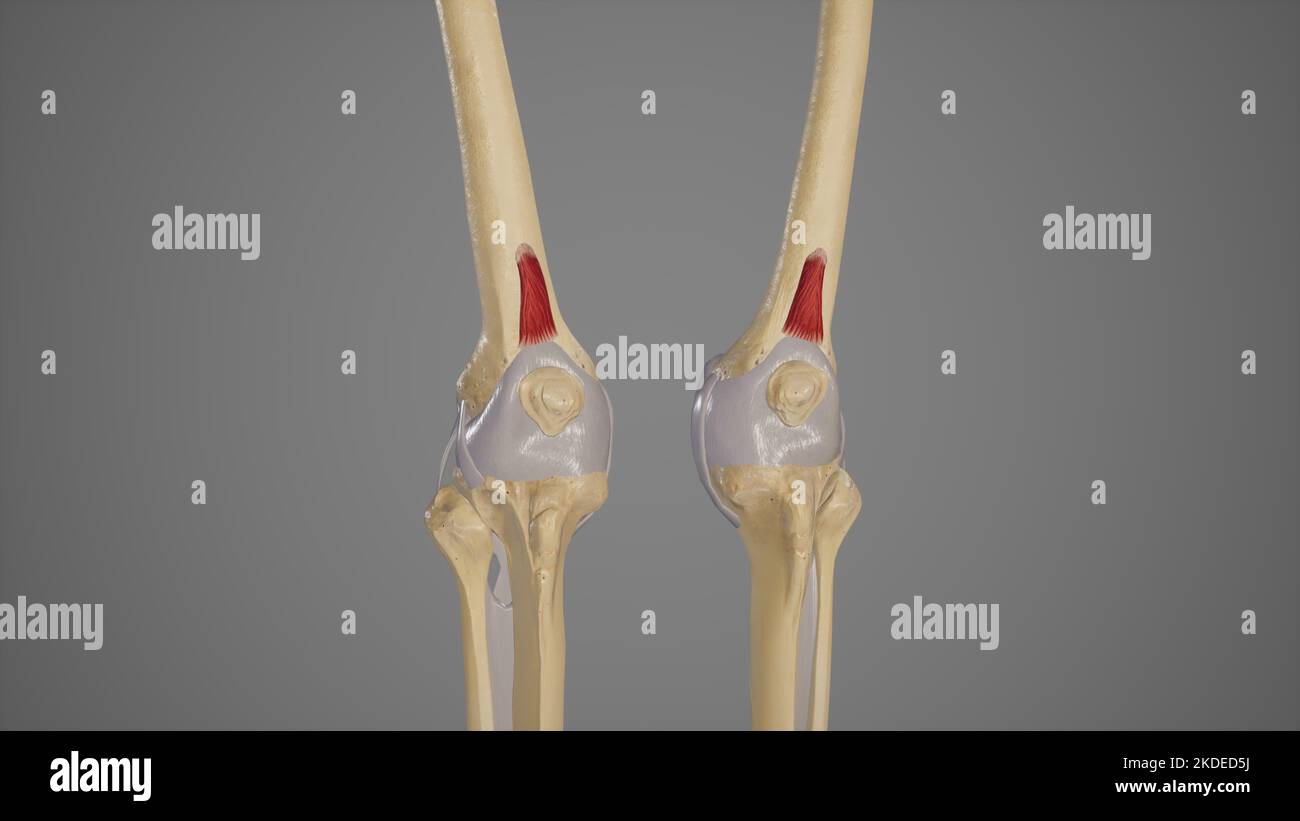

Illustration médicale du muscle du genre Articularis Banque D'Imageshttps://www.alamyimages.fr/image-license-details/?v=1https://www.alamyimages.fr/illustration-medicale-du-muscle-du-genre-articularis-image490198510.html

Illustration médicale du muscle du genre Articularis Banque D'Imageshttps://www.alamyimages.fr/image-license-details/?v=1https://www.alamyimages.fr/illustration-medicale-du-muscle-du-genre-articularis-image490198510.htmlRF2KDED5J–Illustration médicale du muscle du genre Articularis